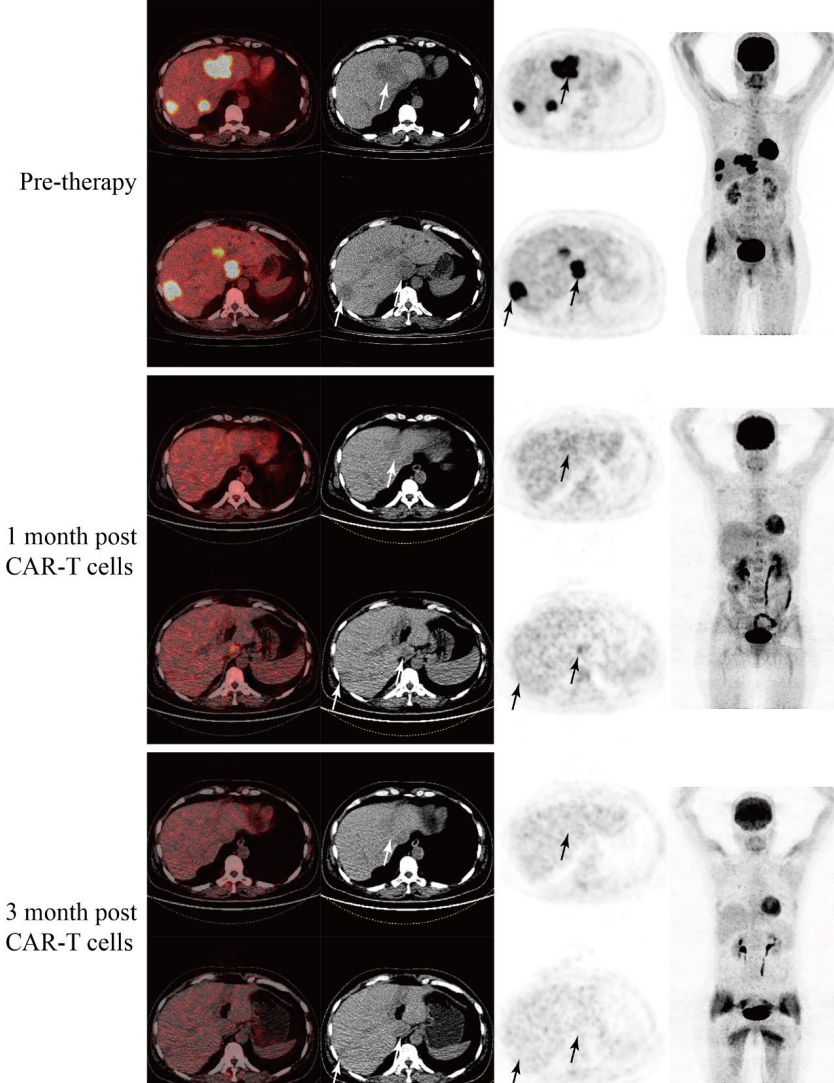

Three months post-treatment, the volume of liver metastases significantly reduced, and the liver lesions showed no FDG uptake, achieving partial remissionLatest research results presented at the 2025 Gastrointestinal Cancer Symposium showed that researchers evaluated two different doses of GCC19CAR-T. In dose group 1 (1 x 10⁶ cells/kg), 4 evaluable patients were included, with an overall response rate (ORR) of 25.0%, where 1 patient achieved confirmed partial remission (PR), and 2 patients showed partial metabolic remission with stable disease (SD); while the performance in dose group 2 (2 x 10⁶ cells/kg) was even more impressive, with an ORR of 80.0% among 5 patients, where one fortunate patient had all tumor target lesions disappear, achieving pathological complete remission! Three lesions significantly reduced, achieving partial remission, and another patient showed complete metabolic remission in PET/CT examination. Overall, across both dose levels (9 patients in total), the ORR reached 56%. The disease control rate was 75% in dose group 1 and 80% in dose group 2, with an overall disease control rate of 78%.